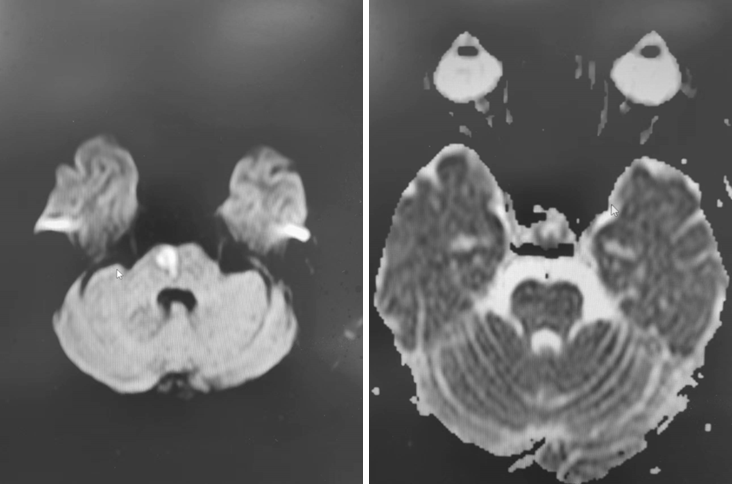

入院影像检查

术前造影:

导丝怎么扩【载药时代 球扩天下】NOVA DES®颅内药物洗脱支架在椎动脉颅内段重度狭窄的应用二例_https://www.jmylbn.com_新闻资讯_第18张

颅脑DWI+MRA:

导丝怎么扩【载药时代 球扩天下】NOVA DES®颅内药物洗脱支架在椎动脉颅内段重度狭窄的应用二例_https://www.jmylbn.com_新闻资讯_第20张

左椎动脉+左颈动脉造影:

导丝怎么扩【载药时代 球扩天下】NOVA DES®颅内药物洗脱支架在椎动脉颅内段重度狭窄的应用二例_https://www.jmylbn.com_新闻资讯_第21张

导丝怎么扩【载药时代 球扩天下】NOVA DES®颅内药物洗脱支架在椎动脉颅内段重度狭窄的应用二例_https://www.jmylbn.com_新闻资讯_第22张

导丝怎么扩【载药时代 球扩天下】NOVA DES®颅内药物洗脱支架在椎动脉颅内段重度狭窄的应用二例_https://www.jmylbn.com_新闻资讯_第23张

右椎动脉造影:

导丝怎么扩【载药时代 球扩天下】NOVA DES®颅内药物洗脱支架在椎动脉颅内段重度狭窄的应用二例_https://www.jmylbn.com_新闻资讯_第24张

导丝怎么扩【载药时代 球扩天下】NOVA DES®颅内药物洗脱支架在椎动脉颅内段重度狭窄的应用二例_https://www.jmylbn.com_新闻资讯_第25张

导丝怎么扩【载药时代 球扩天下】NOVA DES®颅内药物洗脱支架在椎动脉颅内段重度狭窄的应用二例_https://www.jmylbn.com_新闻资讯_第26张

右颈动脉造影:

导丝怎么扩【载药时代 球扩天下】NOVA DES®颅内药物洗脱支架在椎动脉颅内段重度狭窄的应用二例_https://www.jmylbn.com_新闻资讯_第27张

导丝怎么扩【载药时代 球扩天下】NOVA DES®颅内药物洗脱支架在椎动脉颅内段重度狭窄的应用二例_https://www.jmylbn.com_新闻资讯_第28张

右椎动脉动脉正侧位:

导丝怎么扩【载药时代 球扩天下】NOVA DES®颅内药物洗脱支架在椎动脉颅内段重度狭窄的应用二例_https://www.jmylbn.com_新闻资讯_第29张